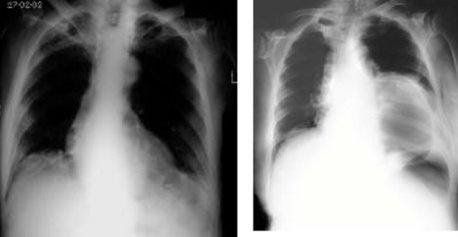

7.1. X quang ngực thẳng, nghiêng:

Hầu hết các trường hợp thoát vị khe hoành đều được chẩn đoán khởi đầu bằng hình ảnh nghi ngờ trên X quang ngực thẳng. Trên X quang ngực thẳng, thoát vị khe hoành biểu hiện bằng hình ảnh một khối mờ nằm sau bóng tim. Khối mờ này có thể có mức nước - hơi hay không.

Hình A: hình ảnh một khối có đậm độ mô mềm và giới hạn rõ nằm sau tim

Hình B: hình ảnh một khối hơi nằm trong trung thất.

Nguồn : A.H.A. Chapman, (2000)